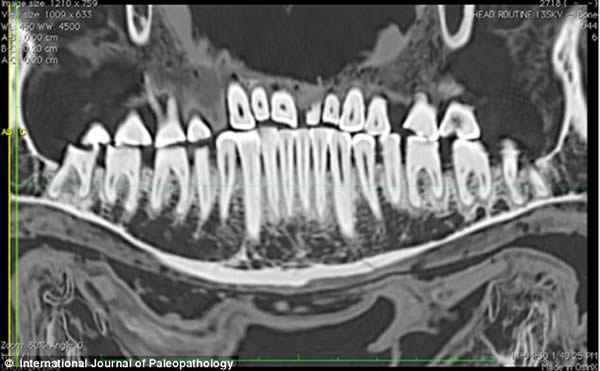

相比过去的研究器材,CT扫描仪使研究团队能够更清晰详尽地观察填充物。

早在20世纪90年代中期,就有研究人员发现了木乃伊口中的小麻布团,但当时的扫描技术太低以至于不能给出更全面的分析,而本次研究使用的高分辨率扫描仪的功能是之前扫描仪的6倍。